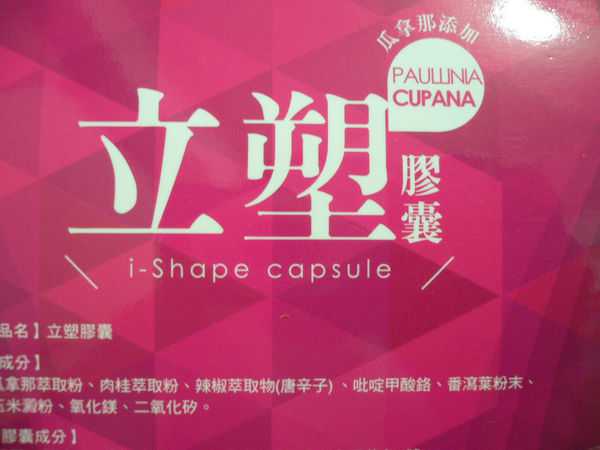

同時,謝謝【女人知己試用大隊】提供的–Supercut塑魔纖立塑膠囊

好啦,廢話不多說,就來試試繽紛小桃紅--Supercut塑魔纖立塑膠囊

Supercut塑魔纖立塑膠囊的成分有:瓜拿那萃取粉、肉桂萃取粉、辣椒萃取物(唐辛子)、吡啶甲酸鉻、番瀉葉粉末、玉米澱粉、氧化鎂、二氧化矽。

那我就跟大家分享瓜拿那萃取粉、肉桂萃取粉和辣椒萃取物吧

瓜拿那萃取和辣椒萃取是可以幫助纖體瘦身常見的營養素!

1.「瓜拿那」是原產於亞馬遜流域的一種藤蔓植物,富含酵素可以幫助排便順暢,並且能抑制脂肪分解酵素,此外也有降低食慾的效果喔~~萃取物中含有天然咖啡因,可以提高新陳代謝率以及排出多餘水分!

2.「辣椒萃取物」則是可以幫助體內脂肪燃燒、增加卡路里的消耗,達到防止脂肪積聚的效果

3.「肉桂萃取物」看到肉桂,就想到麥當勞的蘋果派或是手掌麵包,雖然很多人很害怕那味道,但艾哥愛死肉桂了!!!!肉桂在古代被視為是最有價值的東方香料之ㄧ,中世紀時,肉桂的聲望僅次於昂貴的黑胡椒,除了香料和薰香價值, 傳統上肉也被用來治療消化不良、脹氣、關節疼痛、出血和經痛,研究也指出肉桂可以促進新陳代謝喔